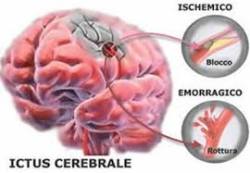

In Italia l’ictus cerebrale rappresenta la prima causa di invalidità ed è la terza per i decessi, dopo le malattie ischemiche del cuore e le neoplasie.. Ogni anno si verificano in Italia circa 196.000 ictus, di cui il 20% sono recidive. Il 10-20% delle persone colpite da ictus cerebrale muore entro un mese e un altro 10% entro il primo anno di vita. Solo il 25% dei pazienti sopravvissuti ad un ictus guarisce completamente, il 75% sopravvive con una qualche forma di disabilità. L’ictus è più frequente dopo i 55 anni, la sua prevalenza raddoppia successivamente ad ogni decade.

In Italia l’ictus cerebrale rappresenta la prima causa di invalidità ed è la terza per i decessi, dopo le malattie ischemiche del cuore e le neoplasie.. Ogni anno si verificano in Italia circa 196.000 ictus, di cui il 20% sono recidive. Il 10-20% delle persone colpite da ictus cerebrale muore entro un mese e un altro 10% entro il primo anno di vita. Solo il 25% dei pazienti sopravvissuti ad un ictus guarisce completamente, il 75% sopravvive con una qualche forma di disabilità. L’ictus è più frequente dopo i 55 anni, la sua prevalenza raddoppia successivamente ad ogni decade.

Ma, l’80% degli ictus può essere evitato riconoscendone immediatamente i sintomi